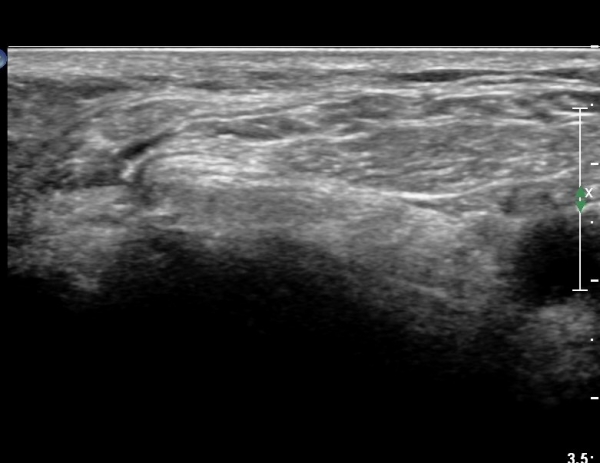

ŽÃËÀÚ¸¦ Á» ´õ ¸»´Ü, ¿ÜÃøÀ¸·Î À̵¿ÇÏ´Ï ºñ°ñµÎ Ç¥Ãþ¿¡¼­ ºñ°ñ½Å°æÀÌ Àú¿¡ÄÚ·Î °üÂûµÈ´Ù(»çÁø 3, 4, 5).